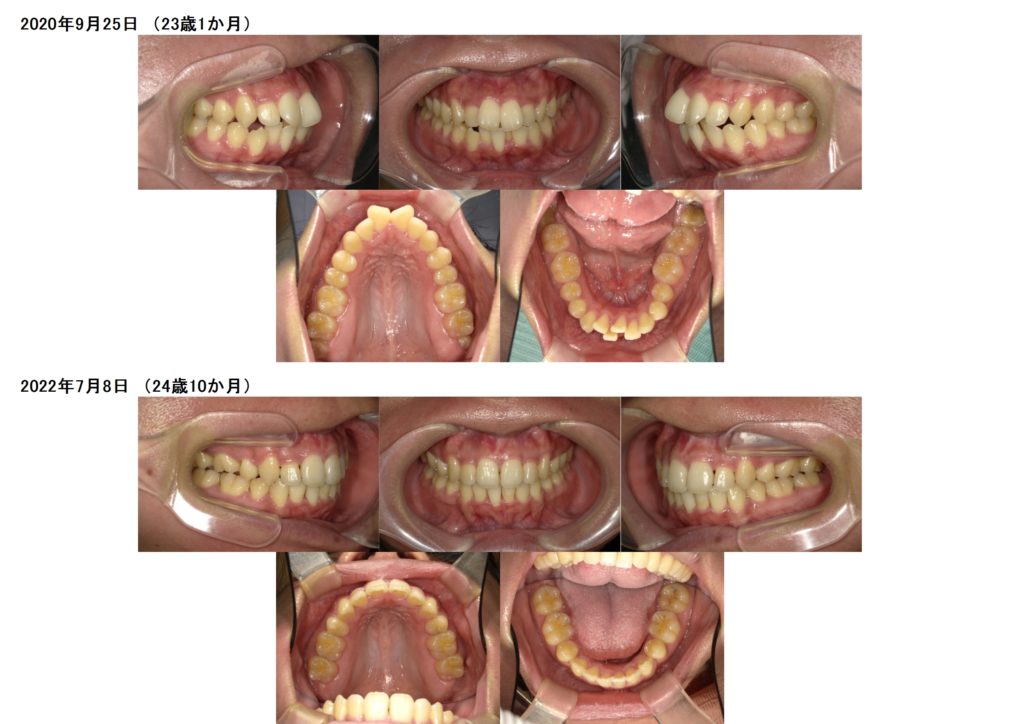

今回はマウスピースでの矯正治療をされた患者さまの治療例です。

上下4番目の歯を抜歯して治療をしました。

少しずつですが確実に前歯も引っ込み、ガタガタ歯並びも治っていますよね。

5カ月ぐらいで噛み合わせも安定しキッチリと並びました。

治療前、治療後の口腔内写真です。

お口元も引っ込み、ガタガタ歯並びも治りました。

横顔もとっても変わりましたよ☆

今は、リテーナーを使用し保定期間中です。

その保定期間もとっても大切な期間になります。